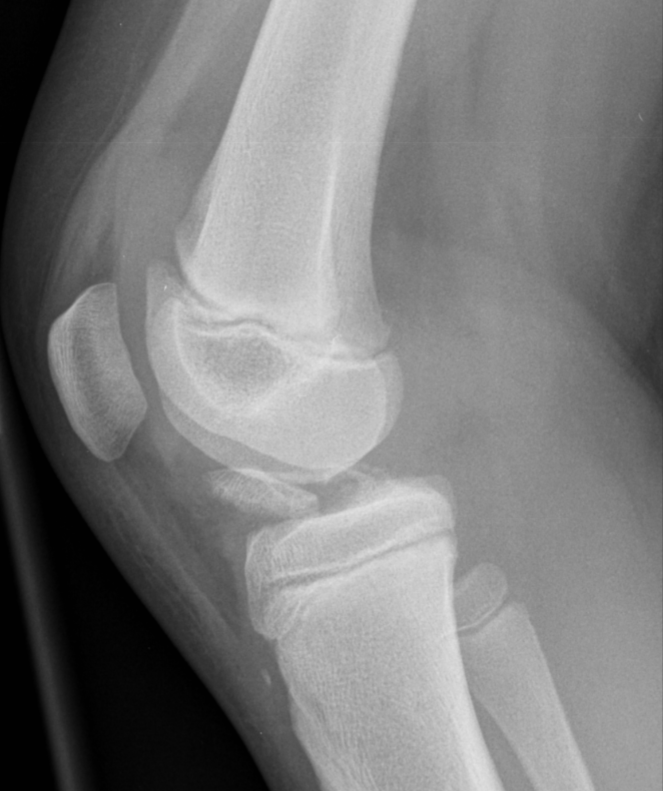

ACL footprint avulsion